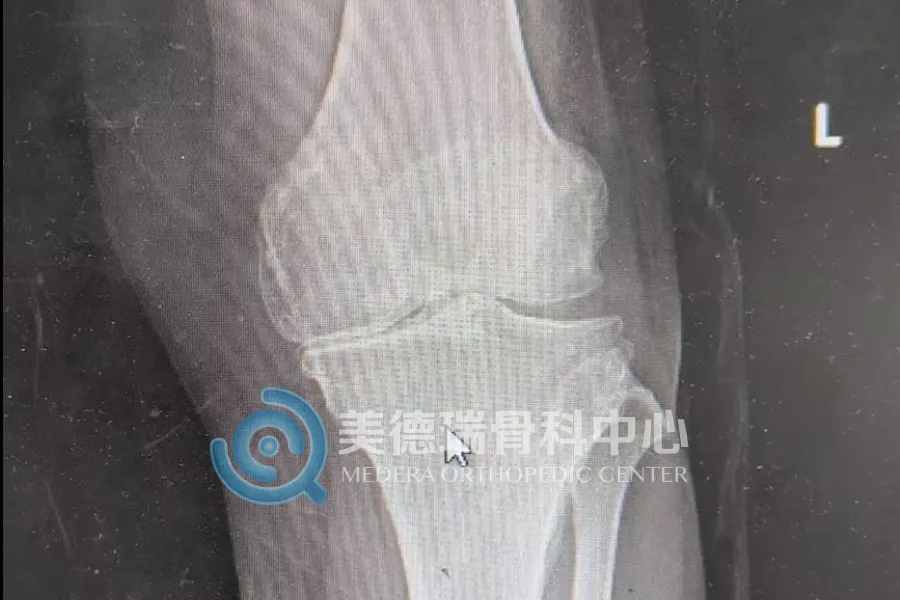

这些患者普遍有一个共同特点,就是病程长、疼痛重、走路越来越困难,日常生活已经受到明显影响。随着关节持续退变,不少患者逐渐出现膝关节变形、行走困难,上下楼和日常活动都受到影响。

重度膝关节骨关节炎发展到后期,关节磨损明显,疼痛会反复加重,腿形和力线也会随之改变。到了这个阶段,全膝关节表面置换术是较为成熟、有效的治疗方式。手术的目标也很明确,就是减轻疼痛,纠正畸形,恢复负重和行走能力。

近期接受治疗的一位68岁患者就是一个典型的例子。双膝疼痛已持续8年,近1个月明显加重,同时合并高血压和糖尿病。入院检查显示,其膝关节退变已较为严重,关节间隙明显变窄,力线也已发生改变,日常行走受到明显影响。经过术前评估和围手术期准备后,美德瑞骨科中心为其实施了全膝关节置换术。术后复查显示,患肢力线得到纠正;从术后站立和行走情况看,患者恢复平稳,已具备早期下地活动条件。